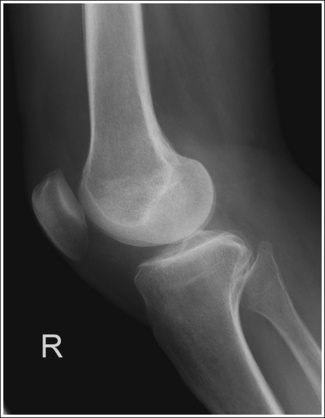

• Distinguishing lateral and medial condyles. The first step you should take when evaluating an image on which the distal condylar surfaces are not aligned is to determine which condyle is the lateral and which is the medial. The most reliable method for identifying the medial condyle is to locate the rounded bony tubercle known as the adductor tubercle. It is located posteriorly on the medial aspect of the femur, just superior to the medial condyle. The size and shape of the tubercle are not identical on every patient, although this surface is considerably different from the same surface on the lateral condyle, which is smooth. Once the adductor tubercle is located, the medial condyle is also identified. Another difference between the medial and lateral condyles is evident on their distal articulating surfaces. The distal surface of the medial condyle is convex, and the distal surface of the lateral condyle is flat.